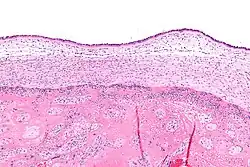

| Micrograph showing acute chorioamnionitis, with neutrophils in the chorion. Also seen are fibrin thrombi, which indicate a severe fetal inflammatory response.[1] H&E stain. | |

Infiltration of the chorionic plate by neutrophils is diagnostic of (mild) chorioamnionitis. More severe chorioamnionitis involves subamniotic tissue and may have fetal membrane necrosis and/or abscess formation.[1]